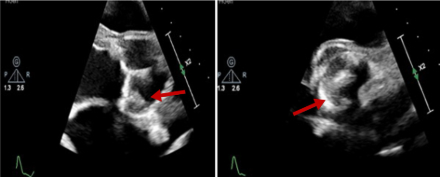

A 56-year-old male with a history of cardiac sarcoidosis with biventricular systolic heart failure (HF) and a bioprosthetic aortic valve presented with acute decompensated HF. Progressive cardiogenic shock and hemodynamic instability ensued, requiring urgent bedside placement of an intra-aortic balloon pump (IABP) which provided only marginal hemodynamic support. After extensive multidisciplinary discussion, emergent cannulation for veno-arterial ECMO (VA-ECMO) was performed at the bedside as a bridge-to-decision for advanced HF therapies. The IABP was left in place for LV venting. Within 72 hours, extensive bilateral pulmonary opacities had developed. It was later realized that true LV ejection (as evidenced by aortic pulsatility on the arterial line) was not present and had been masked by pseudo-pulsatility provided by IABP inflations and deflations. Compared to an echocardiogram done 7 days prior to VA-ECMO cannulation, the bioprosthetic leaflets were no longer opening, thrombosis of the AV had occurred, and thrombus formation along the ECMO venous drainage cannula was noted. Failure to achieve LV venting culminated in complete thrombosis of the entire LV and LA and the patient ultimately expired.